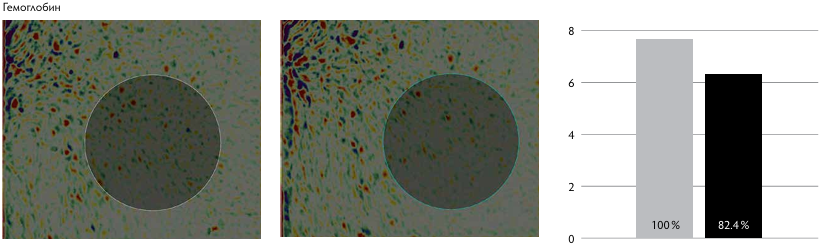

Рис. 1. Показатели пациентов I группы.

Рис. 1. Показатели пациентов II группы.

По данным Miravex Antera, в I группе отмечалось уменьшение содержания гемоглобина в среднем на 52–65 %, что говорит о снижении насыщения кожи поверхностными сосудами. Это свидетельствует в пользу эффективности методики при лечении пациентов с постакне, гиперпиг ментацией, поствоспалительными пятнами.

У пациентов II группы, по данным Miravex Antera, уменьшение содержания гемоглобина отмечалась в среднем на 15–21 %, меланина — на 1–5 %, улучшение текстуры кожи — на 18–25 %, снижение глубины морщин на 15–27 %, что сопоставимо с результатами пациентов I группы. По данным GAIS, у пациентов I группы отмечается удовлетворённость результатами процедуры на три балла, со стороны врача — тоже на три балла. У пациентов II группы пациенты расценивают результат на 2,4 балла, врач — на 2,4 балла.